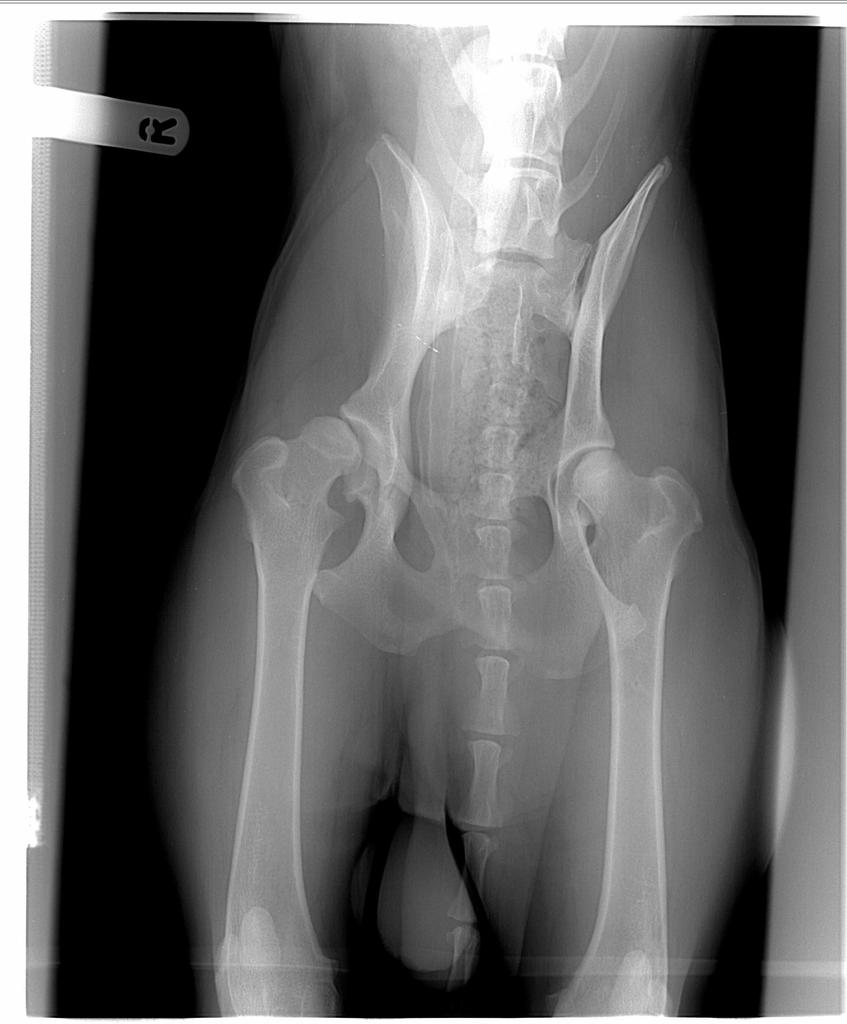

1. Czytajac ten watek narobilam sobie (pewnie niepotrzebnie ) nadzieji. U nas dysplazja prawego biodra (pies 16 miesiecy ). Czy wg was jest jakas szansa, ze pies lezy nieprawidlowo. W UK niestety nie uzywa sie rynienek, pies jest przywiazany sznurkami. Objawow dysplazji (poruszanie sie, wstawanie) nigdy nie zauwazylam, ale wet powiedzial, ze to lekka/srednia dysplazja prawego biodra. Juz pewnie mam paranoje i wmawiam sobie, ze prawa strona psa jest na kazdym rtg wyzej niz lewa- sprowadzcie mnie na ziemi albo potwiedzcie moje przypuszczenia